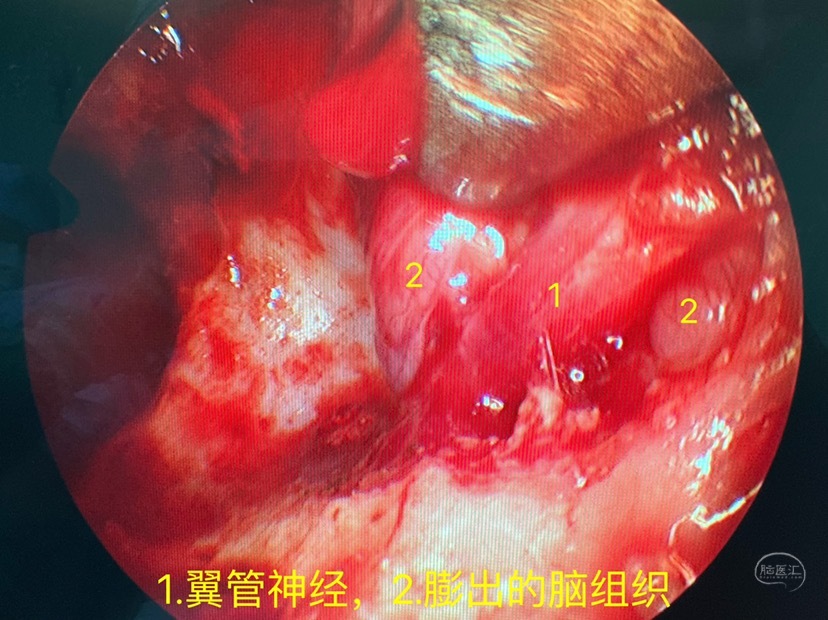

磨开部分翼管骨质显露翼管神经,及其后方膨出的脑组织